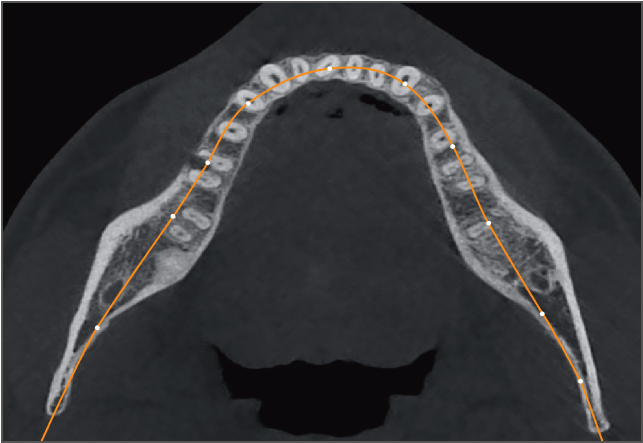

• lamtau AI牙弓曲線

AI牙弓曲線